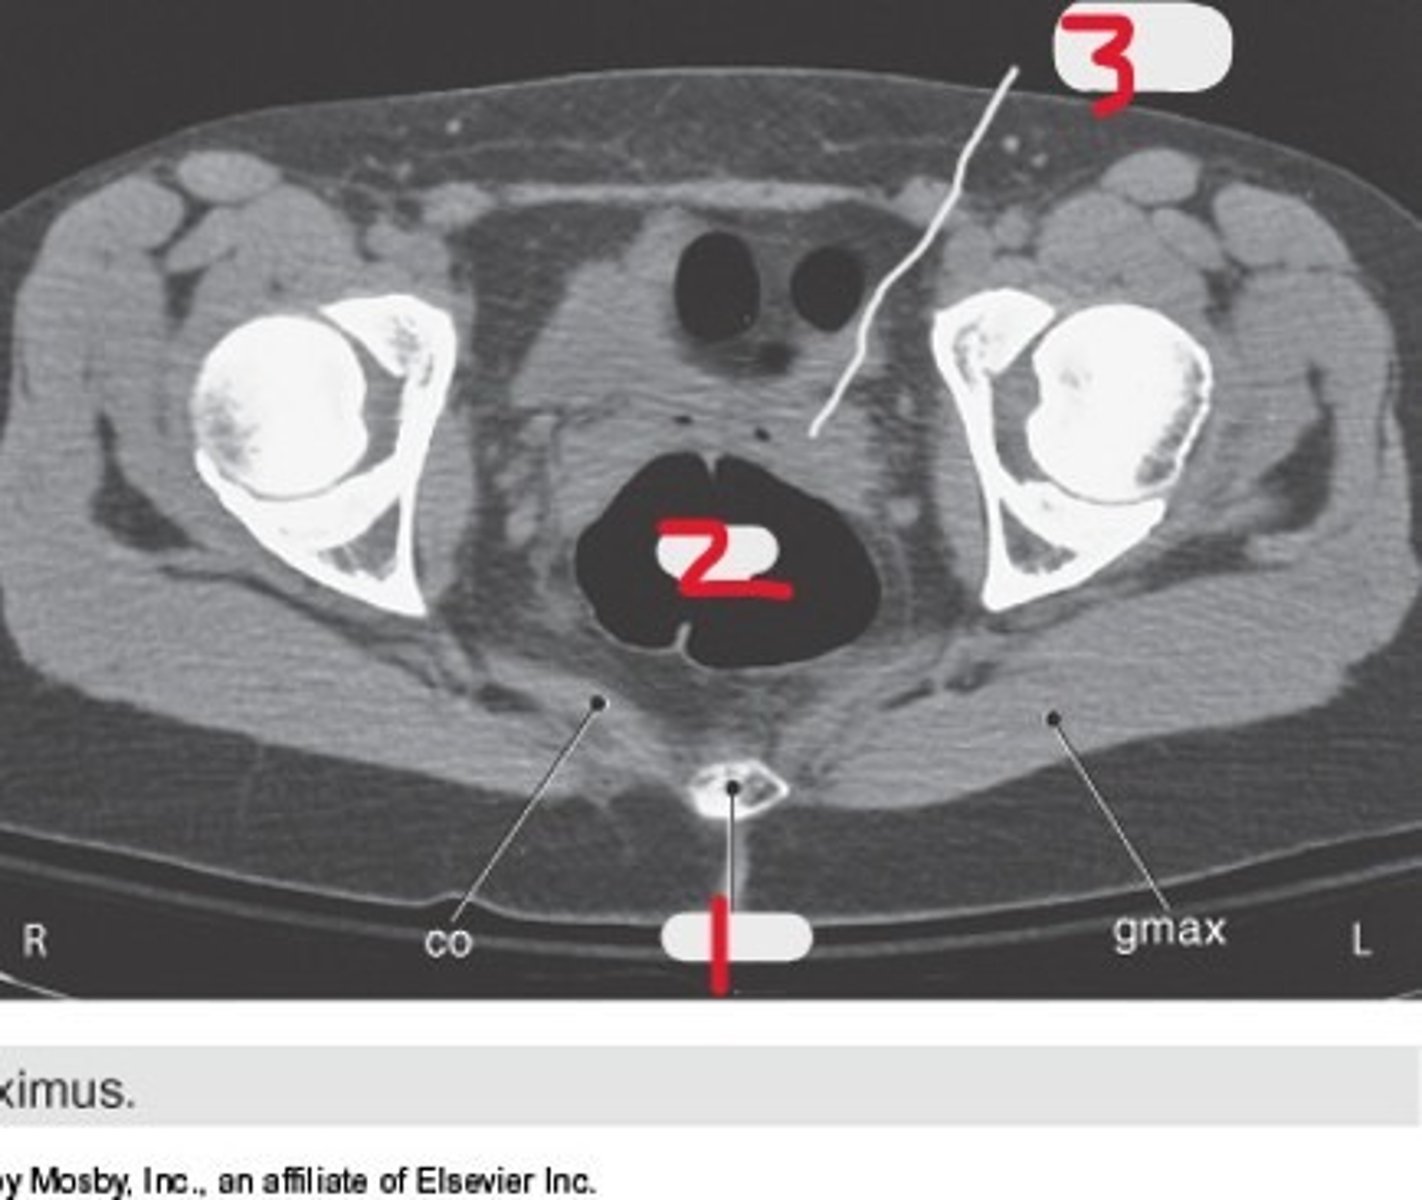

1) Sacral promontory

2) Sacrum

3) Coccyx

Name all numbered structures